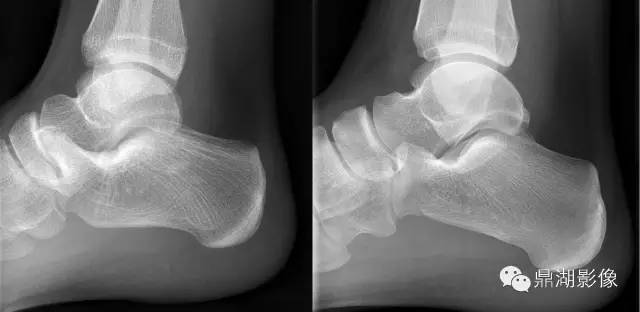

“食蚁兽鼻征”即在足侧位片跟骨前突过长,超过跟骰关节面水平,此征象对诊断跟舟骨桥有很大的帮助,于1987年首先由Oestreich等人提出来。有报道称“反食蚁兽鼻征”,即舟骨向后外侧伸长突出,诊断跟舟骨桥的特异性达 100%

左图为食蚁兽鼻征,右图为正常